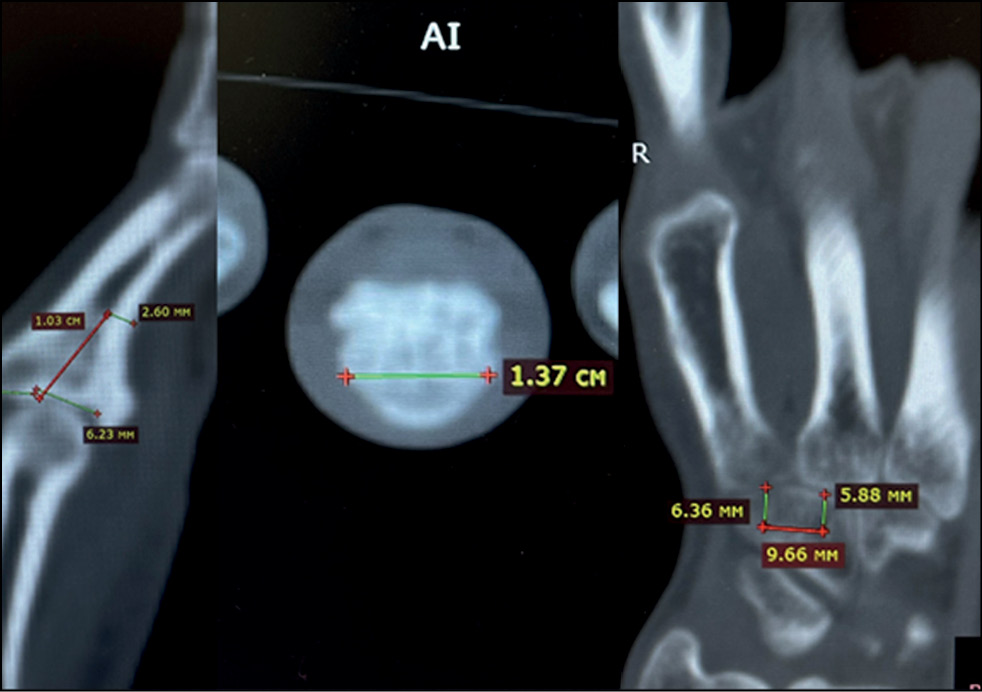

Fig. 9. Analysis and marking of computed tomography.

In the preoperative period, multislice spiral CT was used to determine the spatial visualization of the affected bony anatomical structures of the fingers and the features of malunion fractures of the palmar edge of the base of the middle phalanx of the patient’s triphalangeal fingers. The results of multislice spiral CT are stored in DICOM format and transferred to Dolphin Imaging to form DICOM files. A solid three-dimensional (3D) model of the STL phalanx of the patient’s damaged finger and the necessary bone autograft is formed, showing the affected bone anatomical structures and anomalies of the damaged phalanx made of biocompatible and non-toxic polymer material. Acrylonitrile butadiene styrene, polyethylene terephthalate with glycol, or polylactide is used as biocompatible and non-toxic polymeric material.

Virtual planning of the stages of surgical treatment is performed using the 3D model of the phalanx of the damaged finger and the bone autograft model. Intraoperatively, the same stages of hemiarthroplasty are performed only with the use of an individual fitting template, which allows the most accurate resection of the damaged part of the phalanx and the allocation of the hook bone autograft. This makes it possible to improve the treatment result, speed up the operation, and make it more comfortable for the operating surgeon.

All patients underwent preoperative diagnostics: radiography, computed tomographic study, and clinical evaluation of the range of motion in the joint. According to the radiological and tomographic signs, the fractures of the palmar edge of the base of the middle phalanx with its dorsal subluxation, and in three cases fractures of the dorsal edge of the base of the middle phalanx with palmar subluxation, accompanied by failure of the central bundle of the tendon of the common extensor tendon of the finger, were determined as malunion fractures. According to the Eaton classification, they are categorized as groups IIIa and IIIb. In all cases, the amplitude of movements in PIP joints was sharply limited; flexion was up to 30°. Pain syndrome at the moment of attempted flexion in the joint was assessed by patients ranging from three to four points on VAS.

During preoperative preparation stage, customized 3D templates made of polymer material from the polyacrylate group (MED610) were created for each patient, repeating the exact anatomical landmarks and dimensions of the normal section of the damaged edge of the base of the middle phalanx of the finger, recreated from the same phalanx of the contralateral hand, and, in case of damage to the rear edge, recreated from the middle phalanx of the second toe of the contralateral foot.